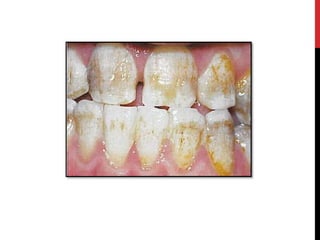

Hypomaturation amelogenesis imperfecta

 Enamel matrix is laid down appropriately & begins to mineralize.

 There is defect in maturation of enamel crystal structure.

• Pigmented pattern

• X linked pattern

• Snow-capped pattern

Hypomaturation amelogenesis imperfecta Enamel matrix is laid down appropriately & begins to mineralize.  There is defect in maturation of enamel crystal structure. • Pigmented pattern • X linked pattern • Snow-capped pattern

• #33 The enamel is softer than normal and tends to chip of from the underlying dentin. Radiographically the affected enamel exhibits a radiodensity that is similar to dentin.

• #34 Pigmented pattern The surface enamel is mottled and agar brown. The enamel often fractures from the underlying dentin. Anterior open bite and unerupted teeth exhibiting resorption are common.

• #35 X linked pattern The affected males exhibits different patterns in the deciduous and permanent dentitions. The deciduous teeth are opaque white with a translucent mottling, the permanent teeth are opaque yellow white and may darken with age.

• #37 Snow capped patterns Exhibit a zone of white opaque enamel on the incisal or occlusal one third of the crown. The affected teeth often demonstrates an anterior to posterior distribution .Both the dentitions are affected.